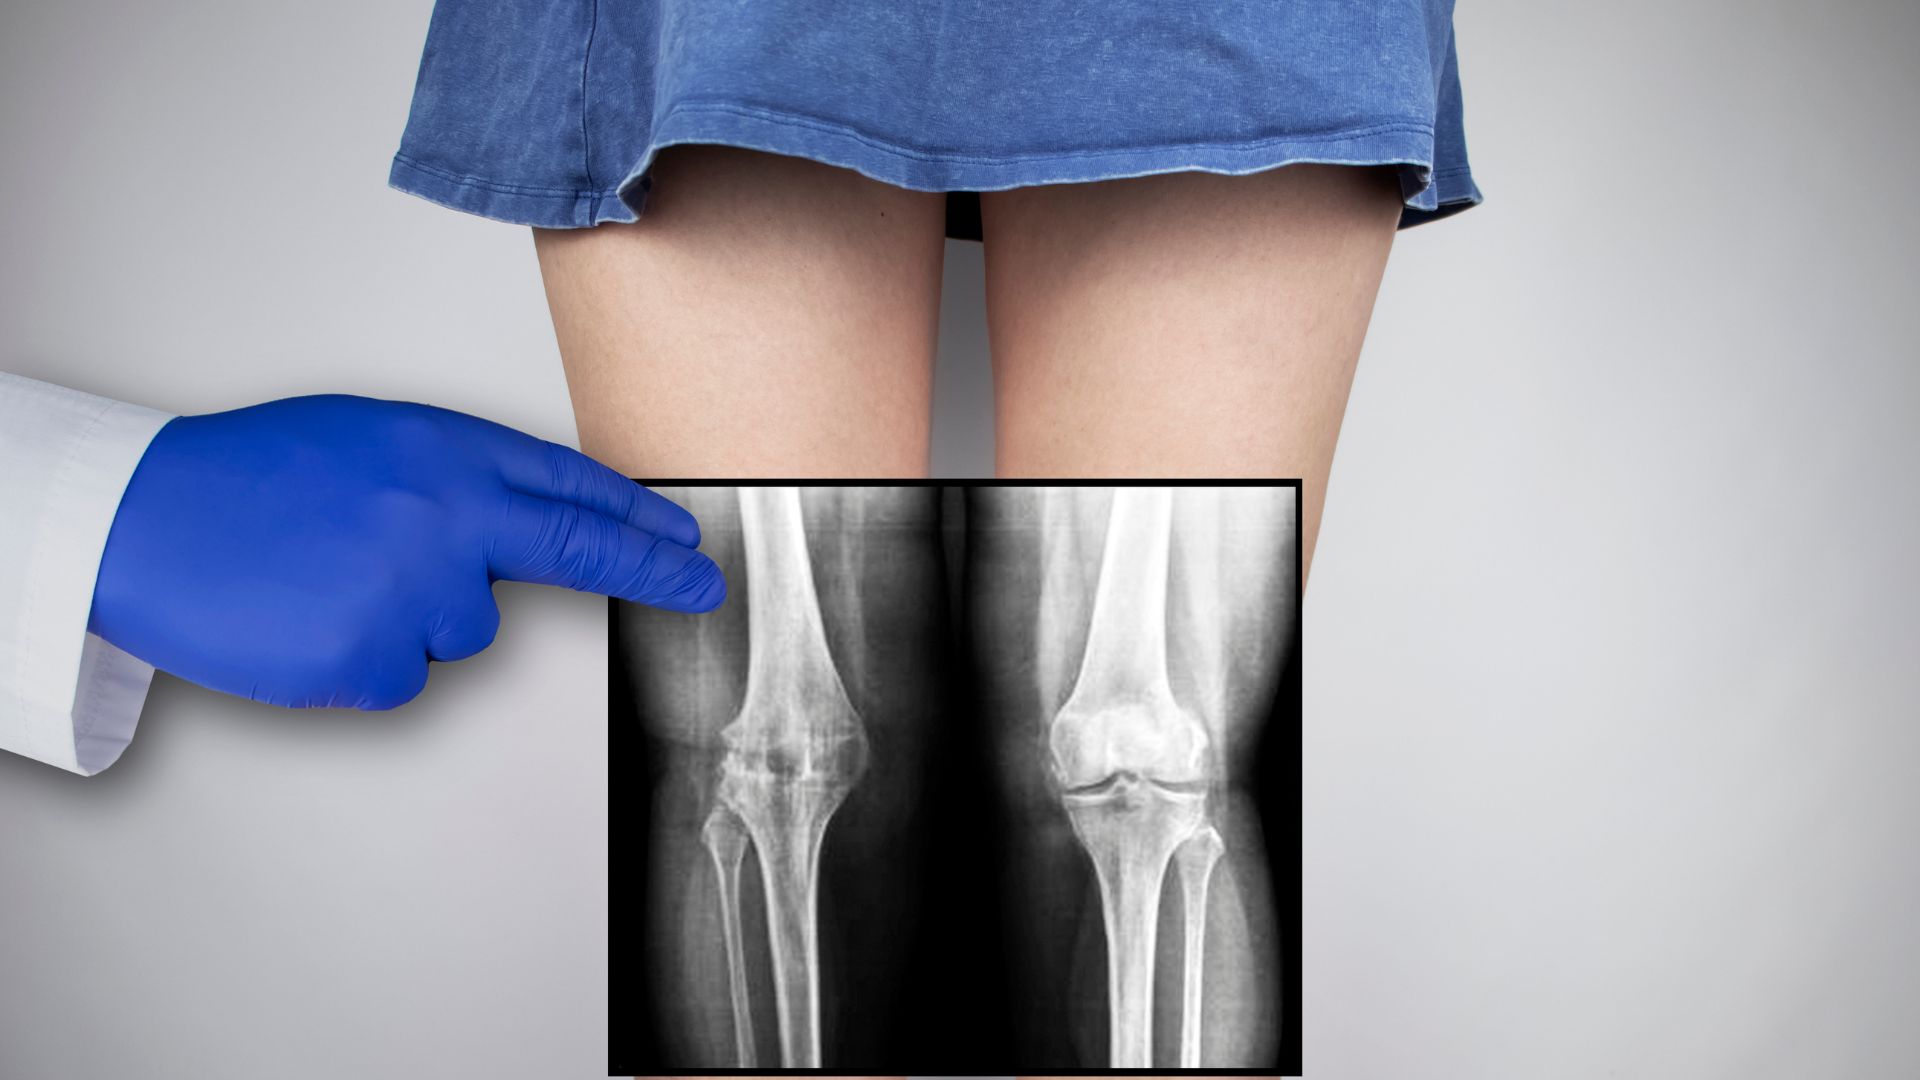

Khi có triệu chứng đau khớp kéo dài không rõ nguyên nhân

Trường hợp người bệnh bị đau khớp gối, khớp vai, cổ tay, cột sống,... kéo dài nhiều tuần mà không có chấn thương cụ thể, bác sĩ có thể chỉ định chụp X-quang để đánh giá tình trạng viêm khớp, thoái hóa khớp hoặc tổn thương sụn, xương dưới sụn.

Vị trí và số lượng vùng cần chụp

Chụp càng nhiều vị trí thì chi phí càng tăng. Ví dụ, chụp một khớp đơn lẻ như khớp gối hoặc cổ tay có chi phí thấp hơn so với chụp cả chi dưới hoặc cột sống. Mỗi vị trí được tính phí riêng biệt, không gộp chung, do đó chỉ định vùng chụp càng rộng thì chi phí càng cao.